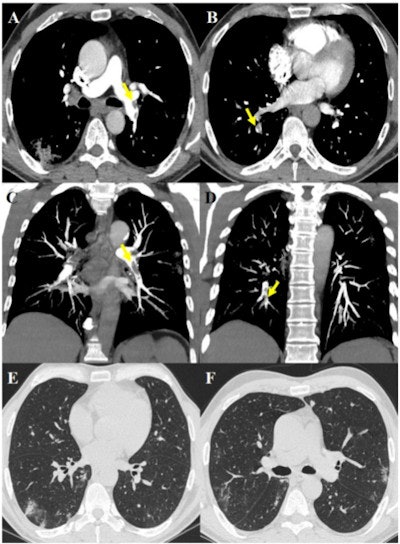

63-year-old male after 17 days of hospitalization without respiratory support and sudden increase of D-dimer value. The images show pulmonary thromboembolism in the lobar arteries for the left lower lobe (yellow arrow, A) and in the segmental arteries for the right lower lobe (yellow arrows, B), confirmed by maximum intensity projection reconstructions (yellow arrows, C and D). Lung parenchyma is characterized by some peripheral subpleural bilateral ground-glass opacities and consolidations (E, F). Images and caption courtesy of the RSNA.

63-year-old male after 17 days of hospitalization without respiratory support and sudden increase of D-dimer value. The images show pulmonary thromboembolism in the lobar arteries for the left lower lobe (yellow arrow, A) and in the segmental arteries for the right lower lobe (yellow arrows, B), confirmed by maximum intensity projection reconstructions (yellow arrows, C and D). Lung parenchyma is characterized by some peripheral subpleural bilateral ground-glass opacities and consolidations (E, F). Images and caption courtesy of the RSNA.The study results may suggest that proactive anticoagulant treatment could be effective for patients with COVID-19, the investigators wrote.